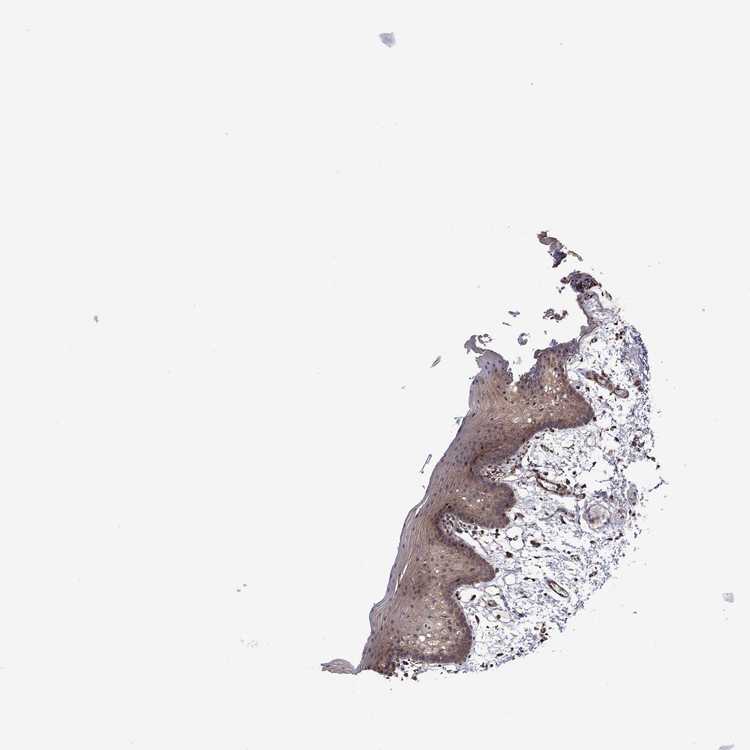

TISSUE PRIMARY DATA ORAL MUCOSA Show tissue menu

ORAL MUCOSA - Antibody stainingi

Antibody staining in the annotated cell types in the current human tissue is reported as not detected, low, medium, or high, based on conventional immunohistochemistry profiling in selected tissues. This score is based on the combination of the staining intensity and fraction of stained cells.

Each image is clickable and will lead to virtual microscopy that enables deeper exploration of all samples and also displays staining intensity scores, fraction scores and subcellular localization as well as patient and tissue information for each sample.

Antibody HPA023314Antibody HPA078682

Squamous epithelial cells LowLow